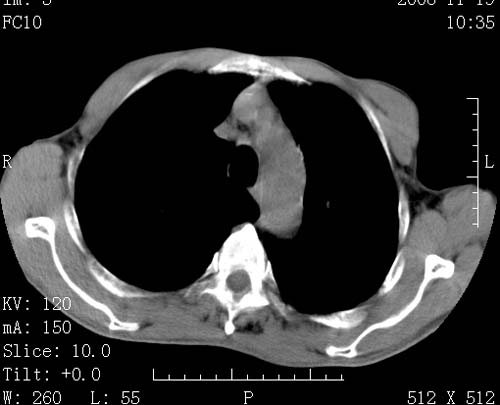

标题: CT16691:m 67 胃镜确诊食管下段及贲门癌 [打印本页]

标题: CT16691:m 67 胃镜确诊食管下段及贲门癌

术前查体,双肺部结节是转移?结核?请点评

1)符合食管癌表现。2)两肺及纵隔淋巴结多发性转移瘤。3)左肺上叶舌段及两肺下叶炎症感染。

食管癌伴双肺转移,评述:肺部毛细血管网丰富,全身血液均快速流经肺部,癌细胞容易过滤定植,形成转移瘤,影象特点为以毛细血管末梢为中心的结节灶,边缘光滑锐利,少见有中心空洞着,不同来源的转移瘤可有各自特点,如甲状腺癌为双肺弥漫性微结节,本例有原发灶,双肺影象灶典型,左肺舌段条带状网格样伴胸膜天幕征,可视为癌性淋巴管炎。